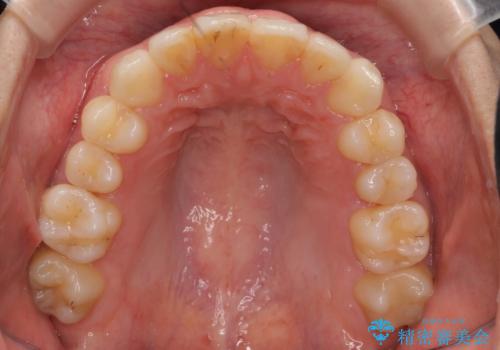

治療も比較的短期間で終わり、大変喜んでいただきました。

下の前歯を1本抜くと上下の正中はあいませんが、ほとんど目立ちません。